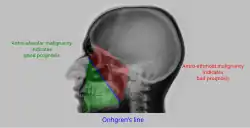

| Pathology | Observation |

|---|---|

| None (Normal) |

|

| Maxillary sinusitis[2] | ![]()

| Polyp |

| Malignancy |

![]()